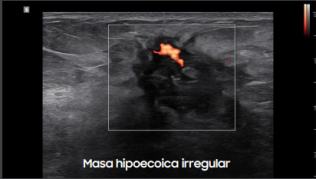

Calidad de Imagen Superior: Claridad, Profundidad y Precisión

El Samsung R20 ofrece tecnologías que garantizan imágenes nítidas, uniformes y de alto contraste en todo momento:

Gracias a estas tecnologías, el R20 garantiza diagnósticos visuales precisos incluso en estructuras complejas o difíciles de visualizar.

Galería de imágenes